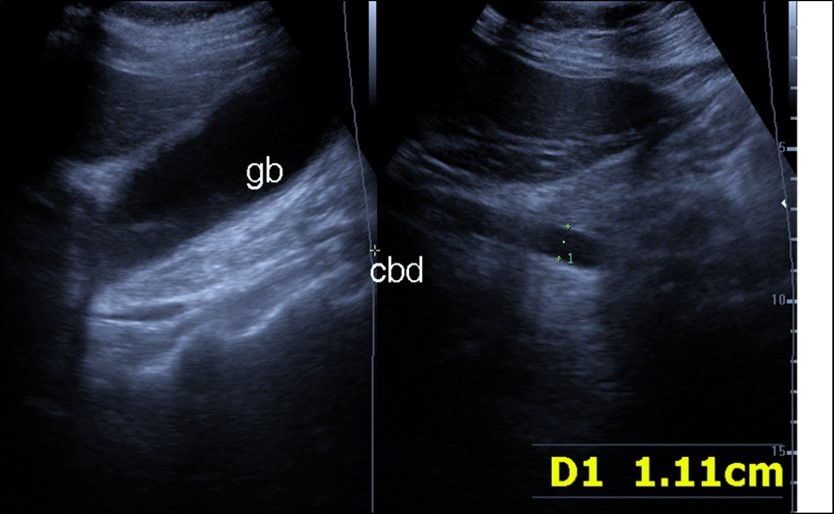

Abdominal ultrasound may revealed any of the followings:-Mild hepatomegaly with echogenic parenchyma and ascites in cases with hepatic impairment (Figure 4, Figure 5) ,thick walls of gall bladder with mildly dilated Common bile duct suggesting of biliary stasis and cholecystitis (Figure 6) .Abnormal renal echogenicity (Figure 7), suprarenal gland enlargements with heterogeneous texture ,splenic wedge shape area of hypoechogenicity ,thickened walls of bowel mainly the rectosigmoid region ,dilated bowel loops with free peritoneal fluid, and gases in the bowel wall with mesenteric and portal vein gases suggesting of bowel wall infarction13.

Figure 4.Real time ultrasound showing thickened wall of gall bladder (gb) with dilated Common bile duct (cbd) in patient with severe Covid-19.

Figure 5.Real time ultrasound showing mild hepatomegaly (li), ascites and thickened gall bladder wall(gb).